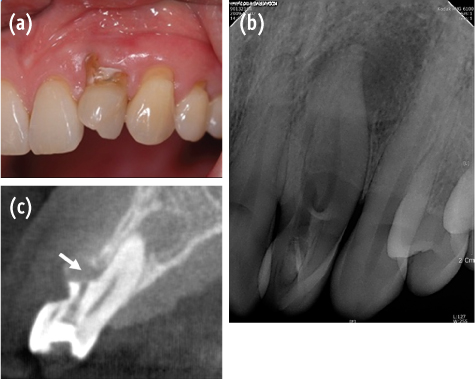

A 46-year-old woman was referred from a private clinic for management of dens invaginatus of the maxillary left lateral incisor. The patient's medical history was noncontributory. The previous dentist created a perforation during access cavity preparation. Clinical examination revealed a non-carious cervical defect incompletely filled with glass ionomer cement (

Figure 1a).

The maxillary left incisor responded negatively to thermal and electric pulp testing (Digitest Pulptester, Parkell Inc, Edgewood, NY, USA). Periodontal probing revealed a normal and intact periodontium. No mobility was noted, and the tooth was not tender to percussion. The periapical radiograph showed a dens invaginatus with a periapical area of radiolucency (

Figure 1b). However, the morphology of the invagination was not clear from the conventional intraoral periapical radiograph. To confirm this unusual morphology, CBCT imaging (Alphard VEGA, Asahi Roentgen Ind. Co., Kyoto, Japan) of the tooth was performed. Informed consent was obtained from the patient. Morphology of the dens invaginatus was evaluated from transverse, axial, and sagittal sections of 0.1 mm thickness.

Figure 1(a) Clinical view of maxillary lateral incisor showing cervical non-carious defect; (b) Radiographic view of dens invaginatus. Periapical radiolucency can be seen; (c) Sagittal CBCT section of the tooth. White arrow indicates the perforation site.